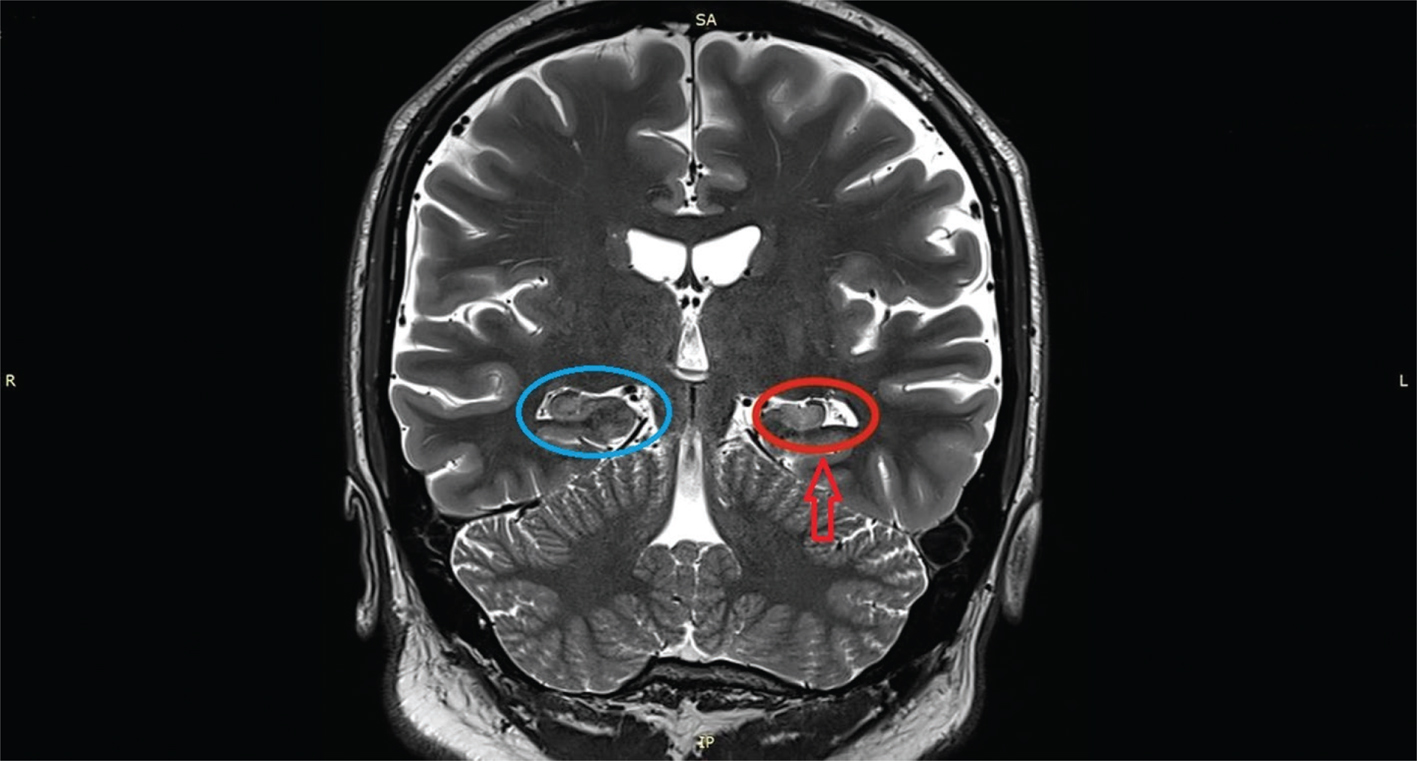

Among structural etiologies, it is noteworthy the relatively frequent finding of hippocampal sclerosis (HS) in mesial temporal lobe seizures (6). The characteristic pathological findings of HS consist of loss of pyramidal neurons and gliosis occurring primarily in the dentate hilus (CA4 subregion) and CA1 subregion with less change in the CA3 subregion (Figure 2). The resulting loss of inhibitory gamma-aminobutyric acid neurons (GABA-ergic) and neuropeptidergic hilar interneurons and the degeneration of excitatory mossy cells induces a synaptic reorganization primarily consistent in mossy fiber sprouting (granule cell axon sprouting) which predominantly projects into the inner molecular layer and hilar region and might establish excitatory feedback loops with the soma and dendrites of normal and ectopic granule cells (10). Mossy fiber sprouting is also linked to granule cell neurogenesis which is acutely accelerated shortly after the epileptogenic insult partly due to a loss of reelin expression by injured hippocampal interneurons (11, 12).

Fig 2

Figure 2. Hippocampal sclerosis as detected by MRI. Note the volume loss (red arrow and red oval) in the left hippocampus compared to the right hippocampus (blue oval). Credit: Uhomachinky, CC BY-SA 4.0 <https://creativecommons.org/licenses/by-sa/4.0>, via Wikimedia Commons.